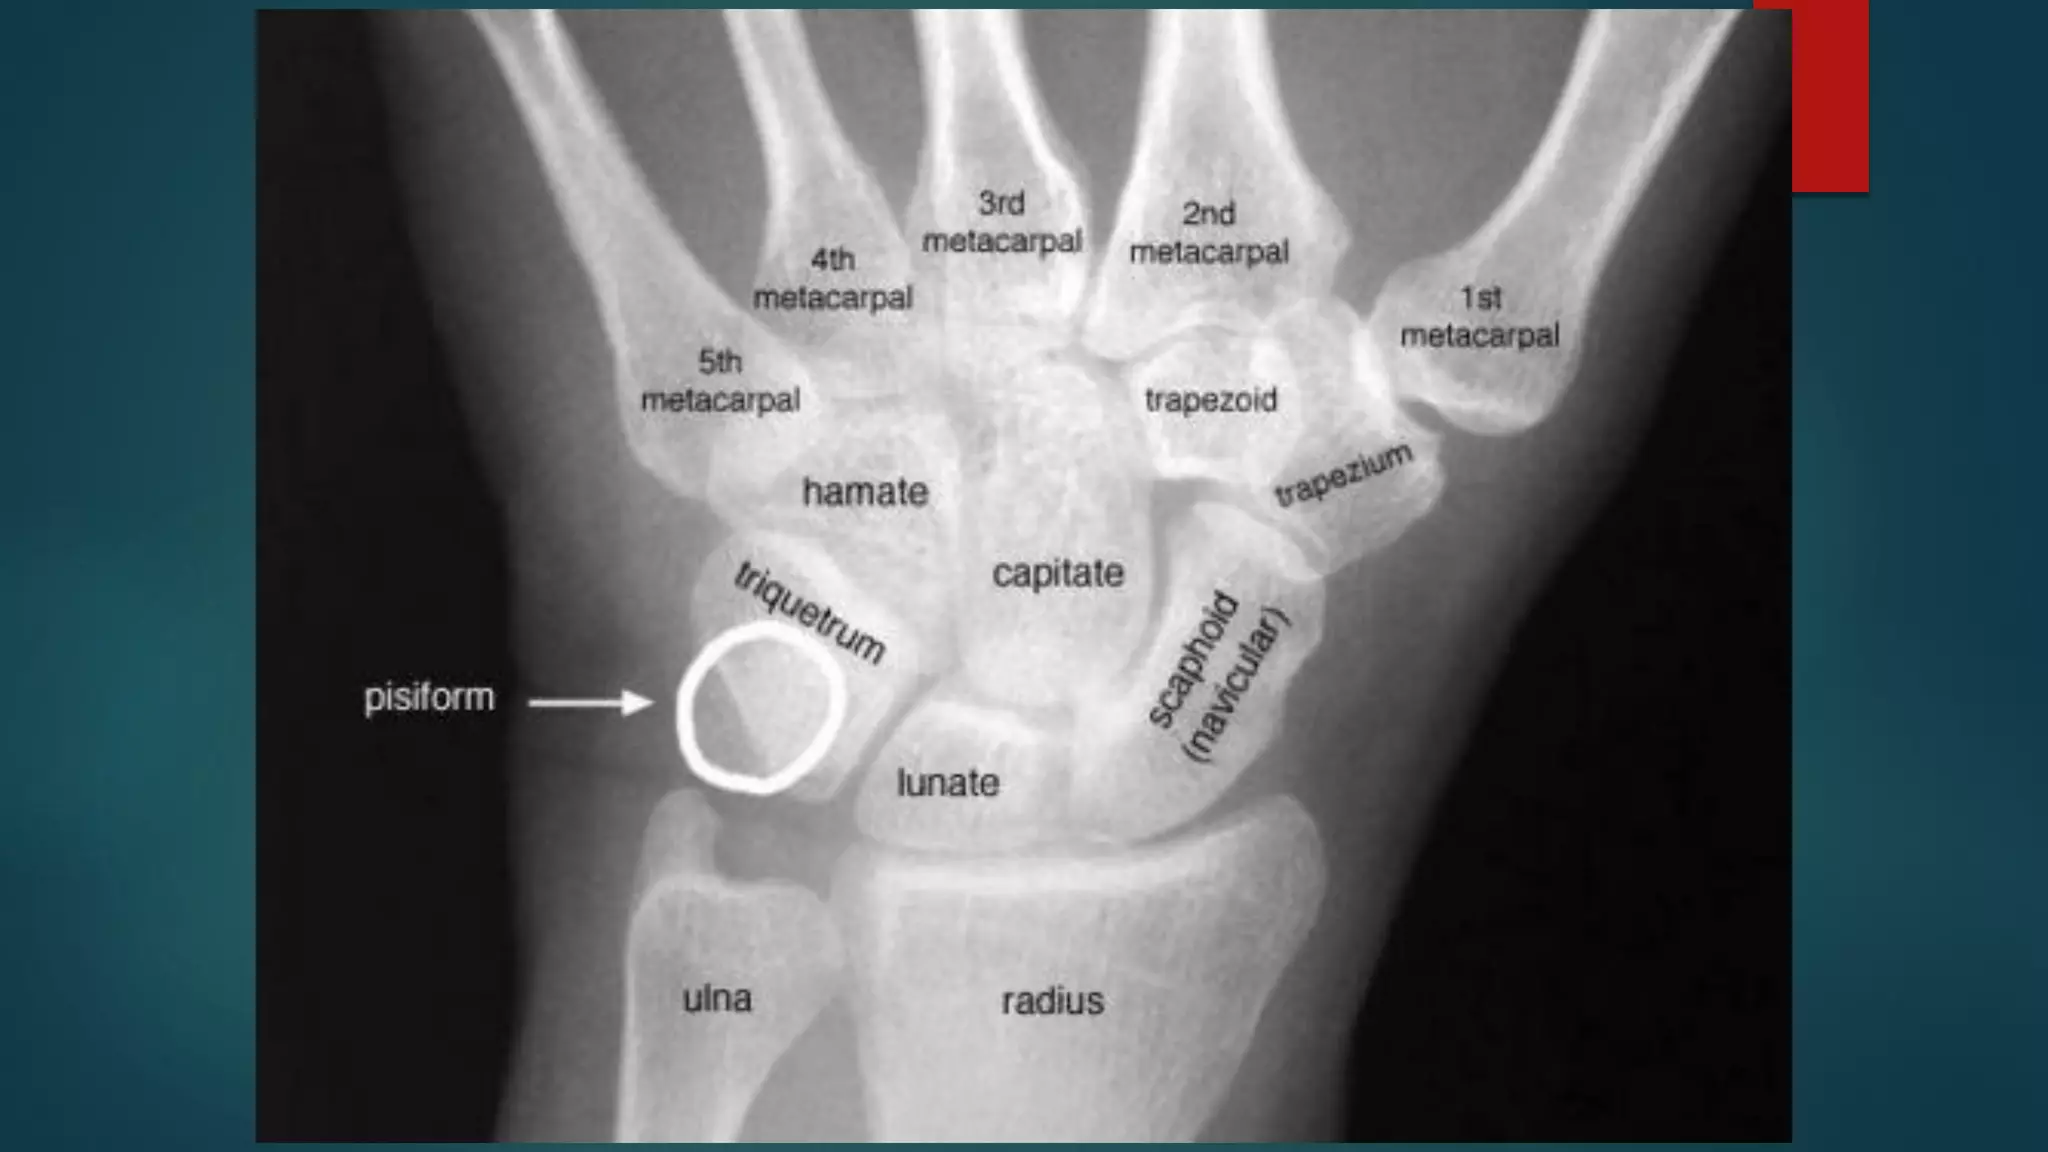

BONY ANATOMY

 Phalanges: 14

 Sesamoids: 2

 Metacarpals: 5

 Carpals

 Proximal row: 4

 Distal row: 4

 Radius and Ulna

BONY ANATOMY  Phalanges:14  Sesamoids: 2  Metacarpals: 5  Carpals  Proximal row: 4  Distal row: 4  Radius and Ulna